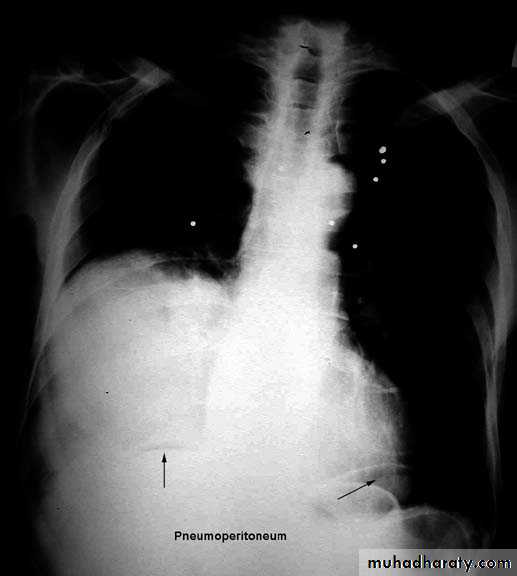

Pleural diseasespleural effusionpneumothorax hydro pneumothoraxpleural calcifications & thickeningpleural tumour

Pleural effusion ( free)